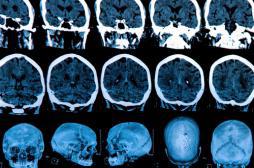

LES MALADIES

SYMPTÔMES